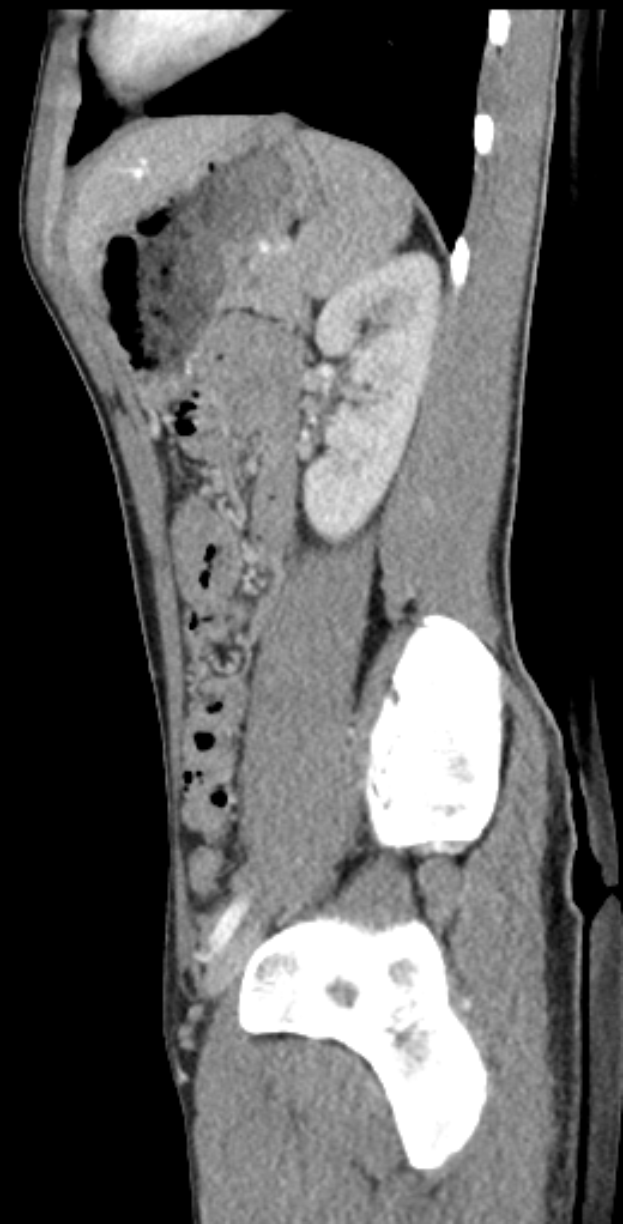

Bei Jan Thielmann begannen die Beschwerden bereits vor dem Anpfiff. Er hatte mindestens einen Tag zuvor über muskuläre Probleme geklagt. Während des Aufwärmtrainings verschlimmerte sich die Situation, sodass er abbrechen musste. Eine anschließende MRT-Untersuchung bestätigte die Muskelverletzung, woraufhin Eric Martel seine Position in der Startelf übernahm.